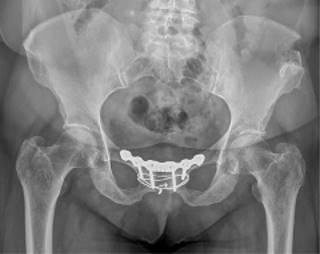

Ambas pacientes fueron mantenidas en descarga durante cuatro semanas, con autorización para carga parcial a partir de la cuarta. Se sometieron a revisiones ambulatorias trisemanales, durante las cuales se observó una reducción escalonada de la analgesia y un aumento en la autonomía para las actividades diarias. En las revisiones, se realizaron radiografías en proyección anteroposterior y en carga (Figuras 8 y 9). A las 12 semanas, iniciaron ejercicios moderados sin impacto. El dolor significativo en la sínfisis del pubis, que inicialmente impedía la deambulación, se redujo gradualmente hasta su completa desaparición, con puntuaciones de 1 en la EVA. No se requirió la retirada del material de osteosíntesis en ninguna de las pacientes durante el seguimiento hasta el momento actual tras dos años de seguimiento.

Figura 8: Radiografía anteroposterior de control postquirúrgico a seis semanas de una de las pacientes. Fusión incipiente de sínfisis.